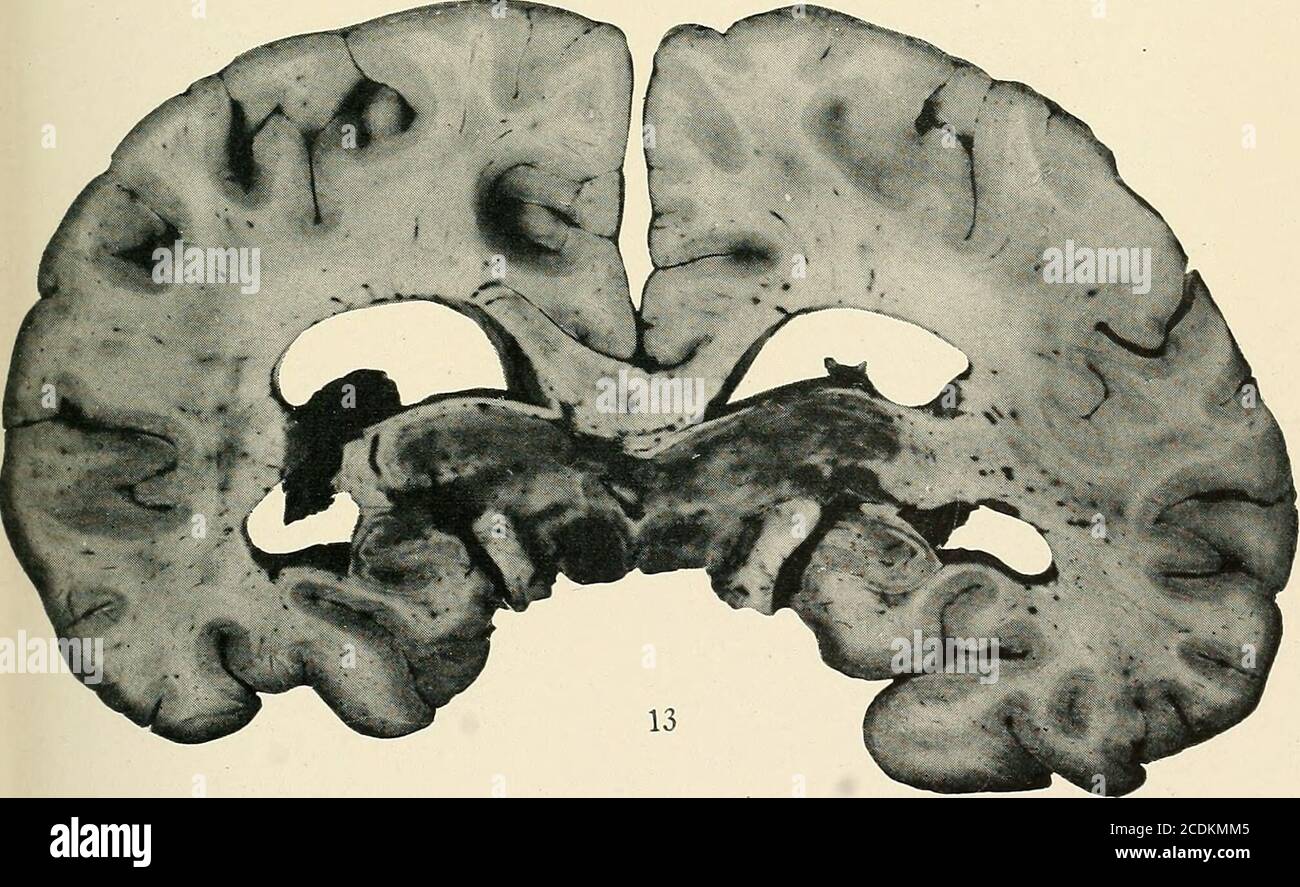

the central nervous system brain

the diencephalon neupsy key

sheep brain frontal slice through massa

diencephalon thalamus chapter 9